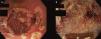

Algunas enfermedades sistémicas como las conectivopatías, vasculitis, enfermedades infiltrativas, enfermedades metabólicas e infecciosas pueden producir afectación gástrica con síntomas y signos difíciles de distinguir de otras patologías. Las enfermedades hepáticas también pueden presentar manifestaciones gástricas, siendo frecuentes las varices, la gastropatía de la hipertensión portal y la ectasia vascular antral. El diagnóstico se realiza principalmente mediante gastroscopia, donde se pueden evidenciar lesiones de aspecto muy variable, siendo la histología clave para el diagnóstico. La escintigrafía es de elección en el abordaje de la gastroparesia. En cuanto a las enfermedades hepáticas, la afectación gástrica suele evidenciarse en la gastroscopia sin necesidad de toma de biopsias. El tratamiento en el caso de las enfermedades sistémicas se basa en medidas de soporte y tratamiento específico de la enfermedad de base. En el caso de las enfermedades hepáticas, el tratamiento es de soporte, precisando en algunos casos fármacos vasoactivos y tratamiento endoscópico específico.

Some systemic diseases, for example connective diseases, vasculitis, infiltrative diseases, metabolic and infectious diseases, may impair stomach physiology causing non-specific symptoms and signs. Similarly, liver diseases may show gastric manifestations, highlighting varicose veins, gastropathy of portal hypertension and gastric antral vascular ectasia. Early diagnosis is mainly performed by gastroscopy, evincing mucosal lesions of varying appearance; diagnostic key is pathologic study. The test of choice for gastroparesis is scintigraphy. Regarding liver diseases, gastroscopy reveals stomach impairing, not being necessary the biopsy. In systemic diseases treatment relies on support therapy and specific treatment of the underlying disease. Support treatment is used in liver disease, requiring sometimes vasoactive drugs and specific endoscopic treatment.